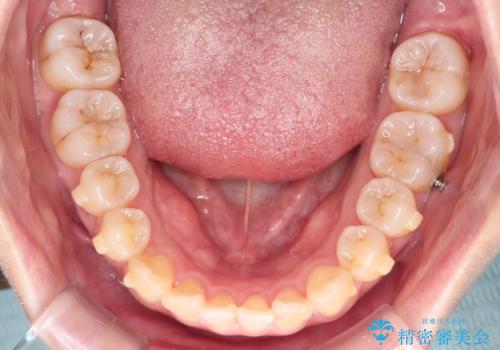

【インビザライン】前歯の凸凹を治したい

- 前歯の凸凹を主訴に来院されました。

インビザラインにて臼歯部の遠心移動を行いながら、できるだけ前歯が出ないように気を付けて治療を行っています。

遠心移動を行う必要があったので、患者様には顎間ゴムを使用していただきました。